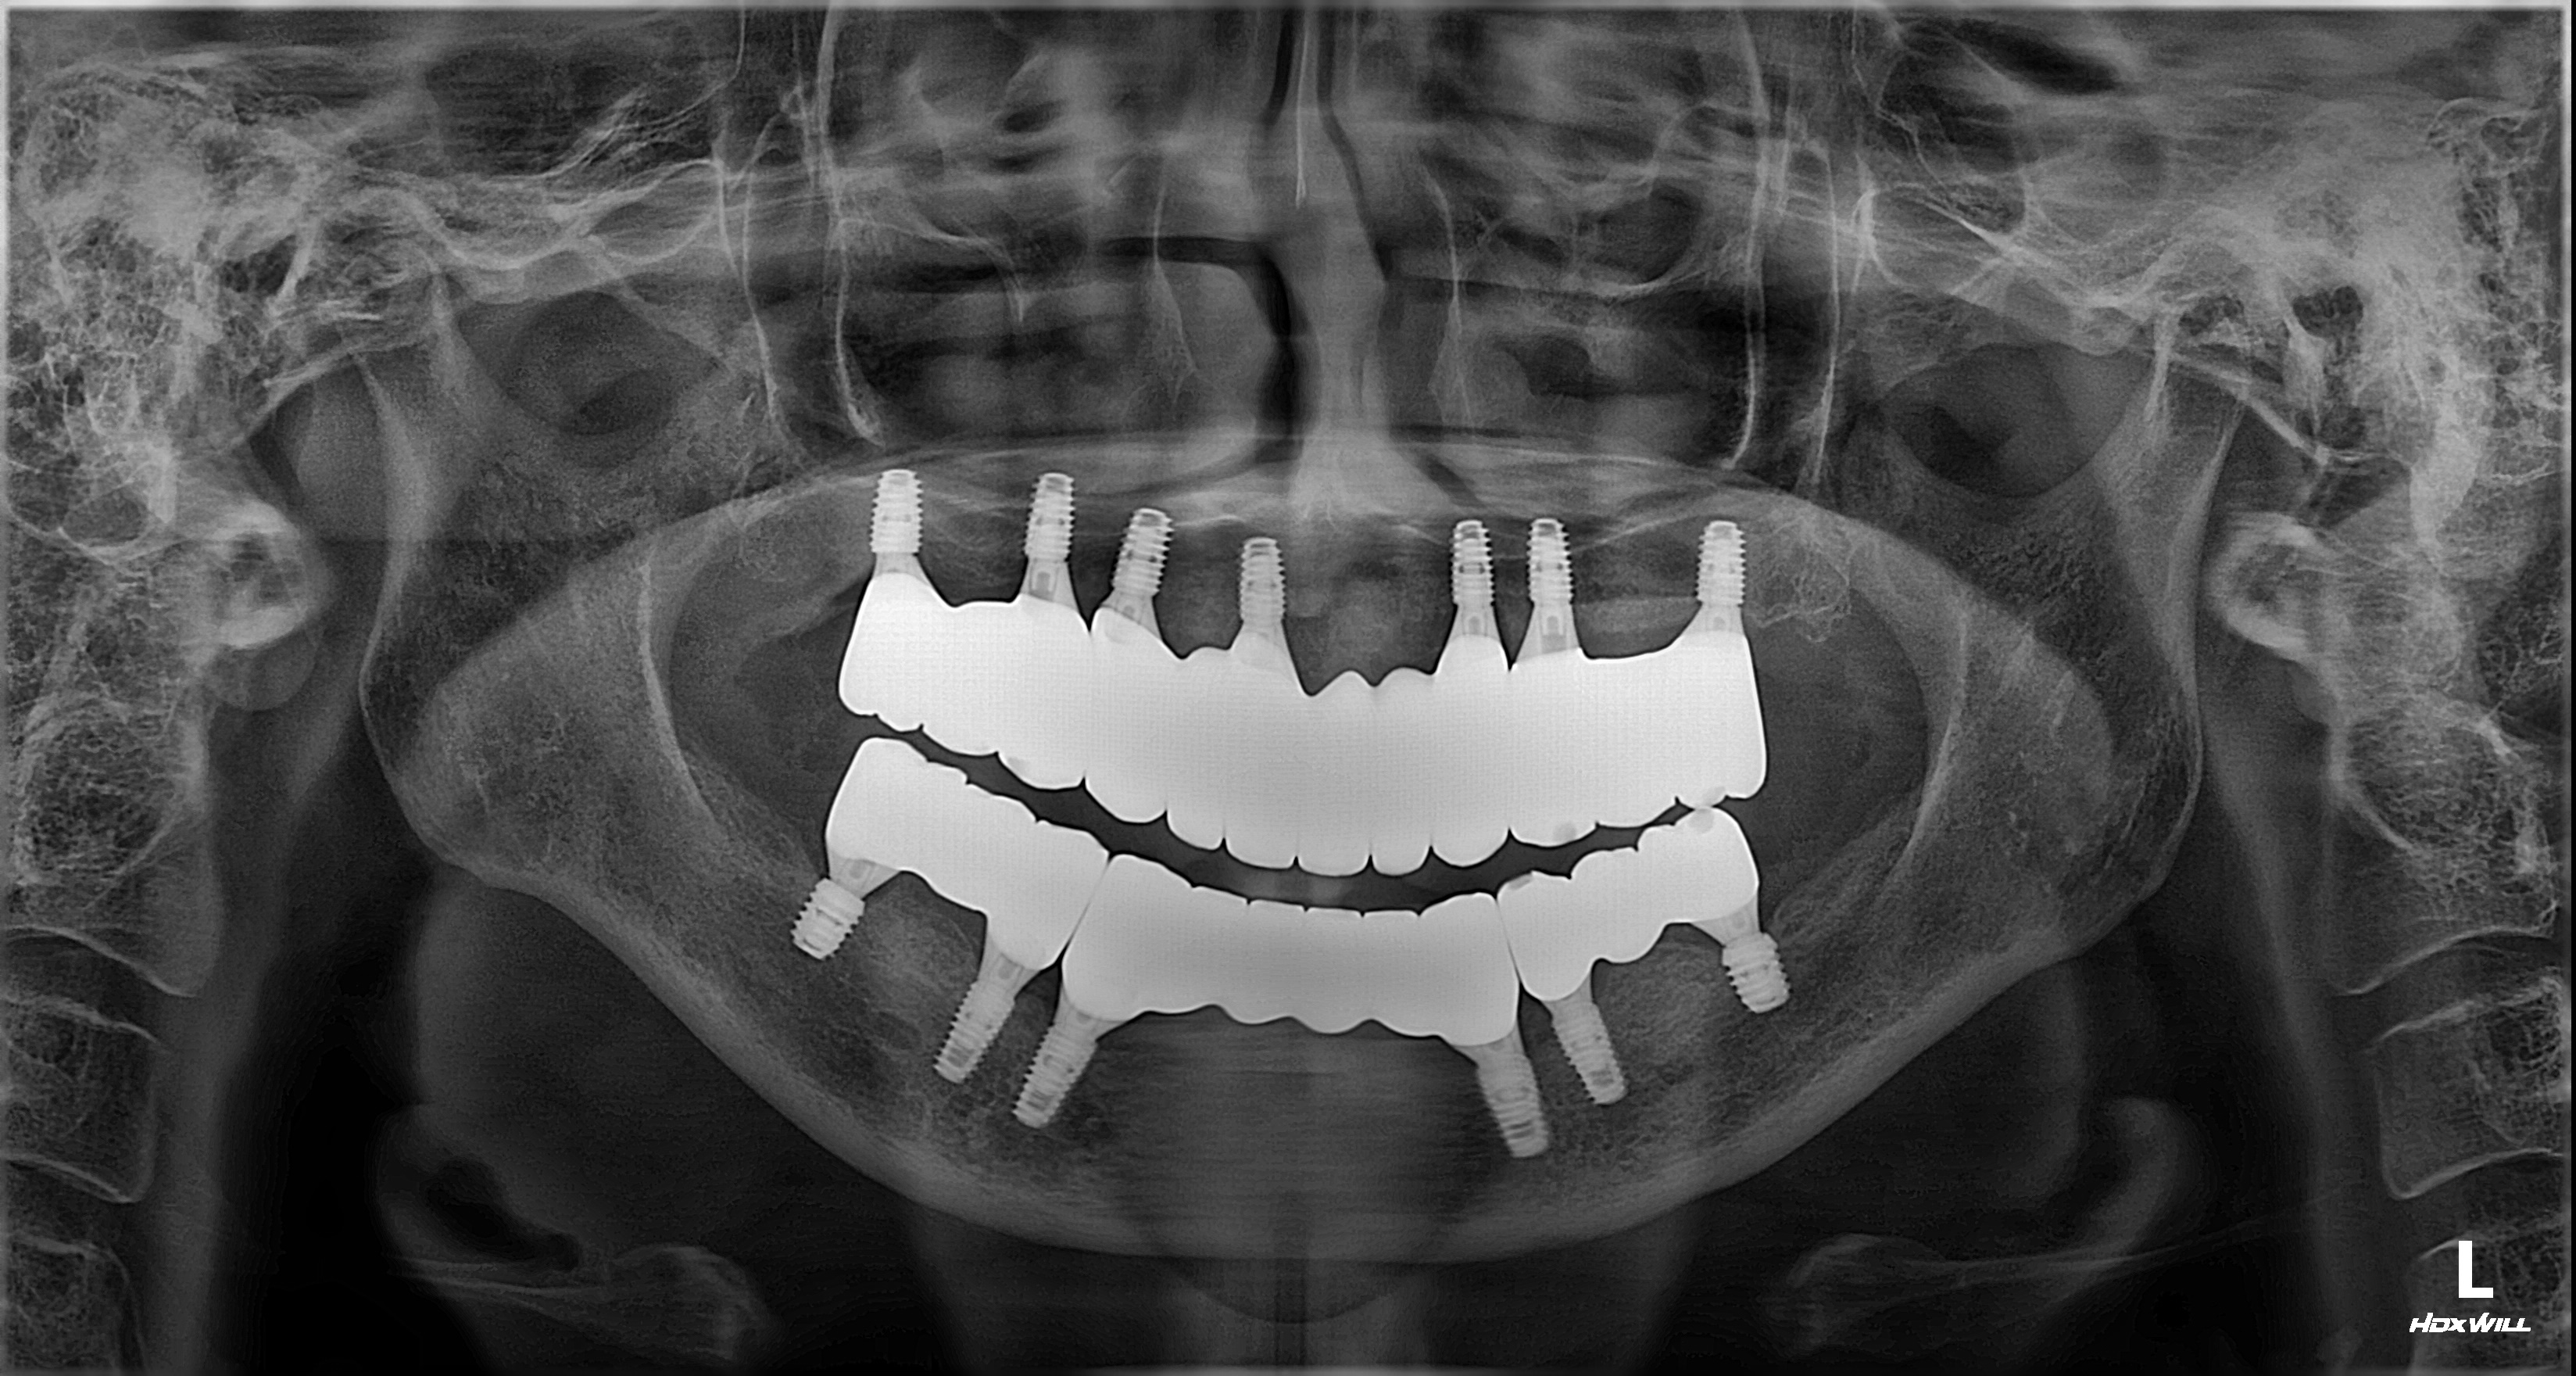

촬영일시: 2025.03.20.

촬영일시: 2026.02.27. [ 치료기간: 2025년 04월 17일 ~2026년 02월 27일 ] ※ 365서울앞선치과의원의 모든 컬럼은 각 진료과 의료진이 직접 작성합니다. 365서울앞선치과의원 임상 케이스 게시물은 환자분께 의학적으로 정확하고 상세한 정보를 드리기 위해 각 진료과 의료진이 직접 작성하며, 모든 증례 사진은 본원 의료진이 직접 시술한 증례를 촬영한 것으로, 의료법 제23조, 제56조에 의거하며 환자분의 동의를 얻어 포스팅에 사용하였습니다. 또한 해당 케이스는 본 환자분의 치료 결과이며, 환자 상태에 따라 치료의 결과는 달라질 수 있습니다. |